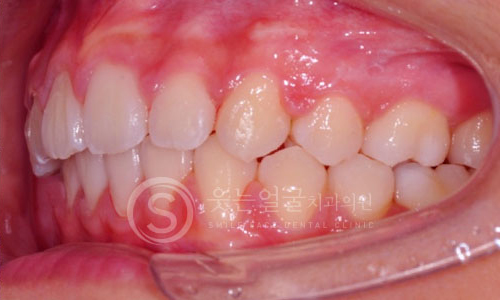

한눈에 보는

임플란트 전후사진